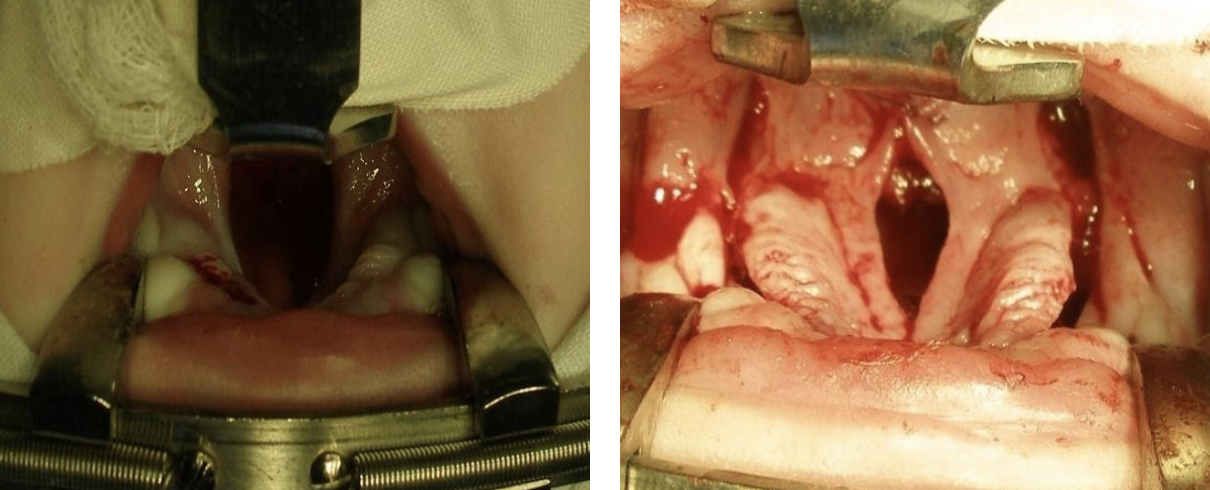

Приклад одномоментної операції SRFM та ураностафілопластики

Дитина з ковтальними та дихальними розладами до операції

під час операції

після операції

Інший приклад.

Приклад операції SRFM без ураностафілопластики (вкрай важка форма, до операції накладена трахеостома)

Після операції на 5-й день.